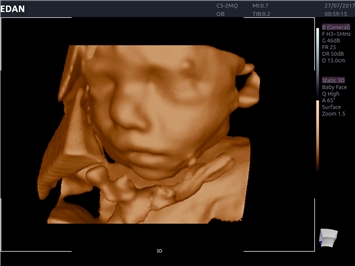

• 3D/4D-визуализация с автоматическим редактированием объема (eFace)

• Акушерства и гинекологии